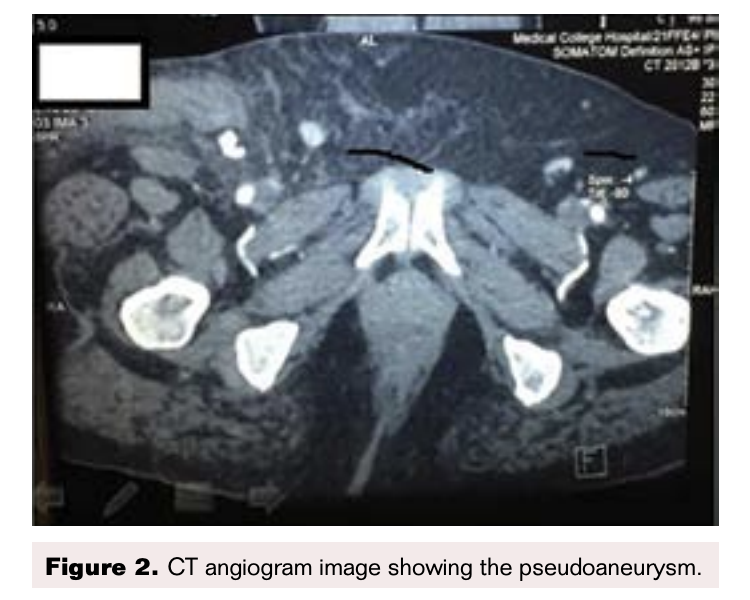

On the ultrasound arterial doppler a heterogeneously hyperechoic area was found at the upper part of the right thigh, with skin discoloration suggestive of a hematoma. This had a well-defined echogenic area with a Ying and Yang color flow, and swirling suggestive of a pseudoaneurysm. This appeared to arise from the common femoral artery (Figure 1). Since the swelling was very large, to enable further treatment decisions we sent the patient for a CT angiography of the thigh (Figures 2-5).

CT Angiogram Findings

A pseudoaneurysm arising from anterior aspect of the right common femoral artery (CFA) just above bifurcation was observed with a sac noted in the subcutaneous space that measured 1.9 x 1.4 cm. A tract from this sac had a length of 2.6 cm and arose from the CFA. A hematoma was noted in the anterior and medial aspect of the thigh in the subcutaneous space adjacent to the pseudoaneurysm (Figures 2-5).